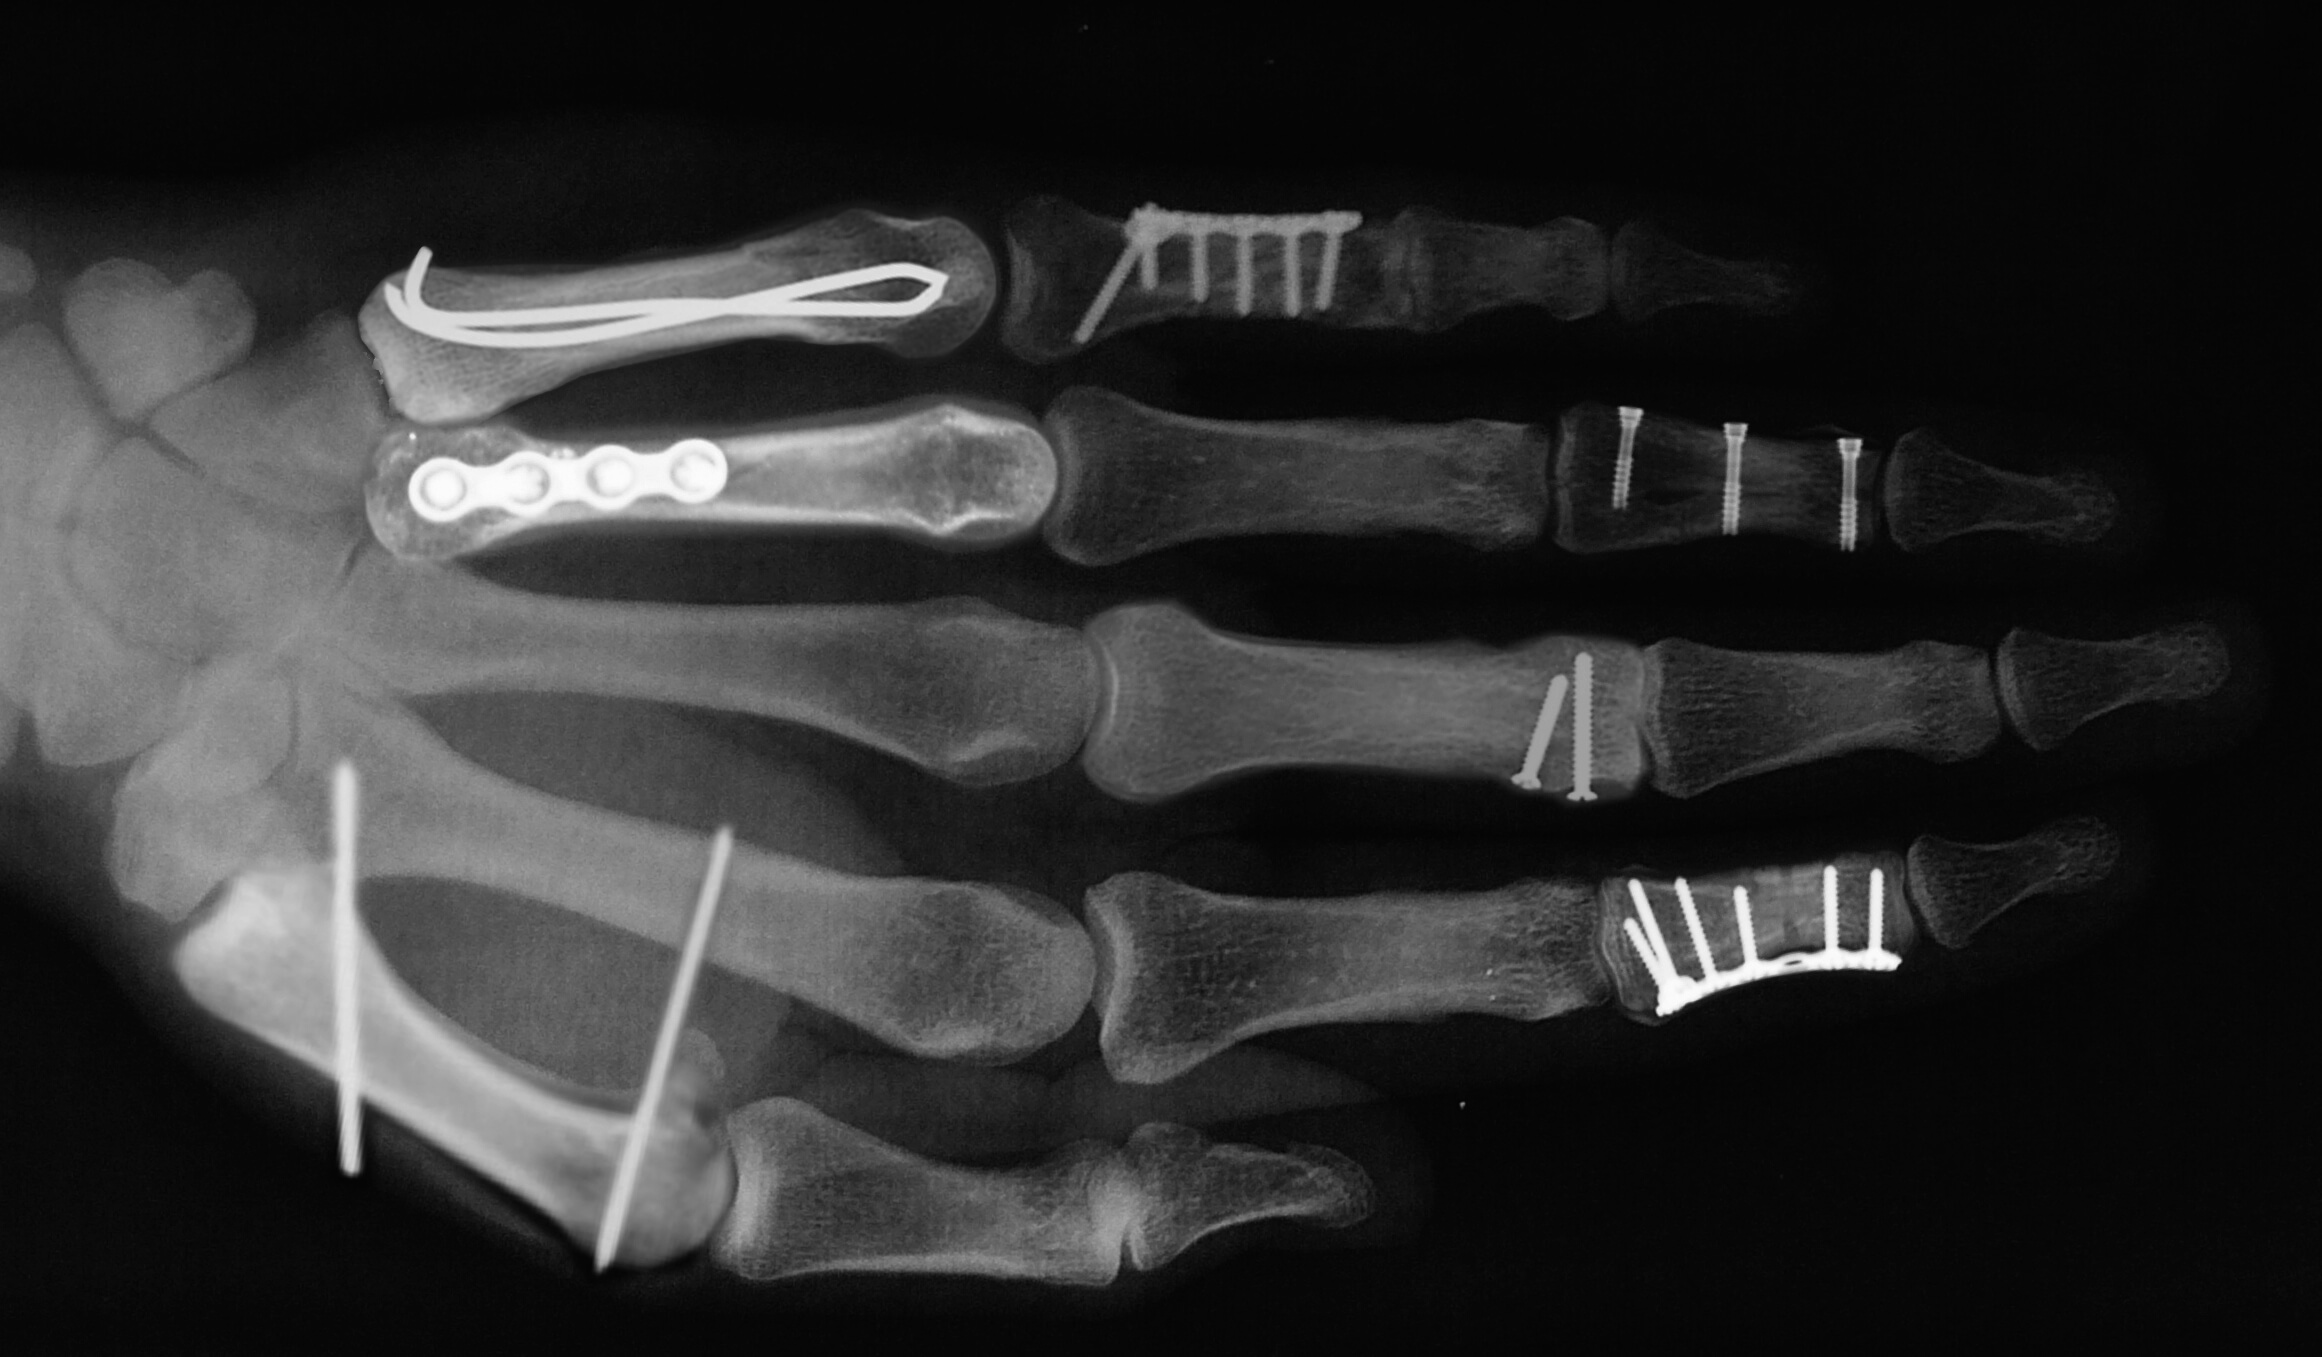

Exemple de fractures et de stabilisation chirurgicale

D’autres fractures peuvent nécessiter une incision plus grande, pour aborder le foyer de fracture et remettre les pièces osseuses correctement. Une fois alignés, les fragments osseux sont stabilisés par du matériel (broches, vis, plaques et vis, ...). Lorsqu’une articulation est fracturée, il faut envisager une restitution la plus précise possible de la surface articulaire. Parfois, il peut manquer de l’os, ou celui ci a été tellement endommagé qu’il ne peut pas être réparé. Dans ces cas, une greffe osseuse est nécessaire, et le chirurgien prélève de l’os à un autre endroit (poignet, coude, bassin) pour combler la perte de substance osseuse et favoriser la consolidation de la fracture.

Certaines fractures qui ont été réduites peuvent être stabilisées par un « fixateur externe », qui est un ensemble rigide de tiges métalliques et de broches fixées dans l’os au-dessus et en-dessous du foyer de fracture. Le fixateur est laissé en place jusqu’à guérison de la fracture, et sa configuration peut être modifiée en fonction des besoins. Une fois que la consolidation de la fracture est suffisante, des exercices de mobilisation des doigts peuvent être débutés pour limiter l’enraidissement. Le chirurgien de la main détermine le moment adéquat pour commencer cette rééducation, en fonction des contrôles en consultation, à l’aide de radiographies.